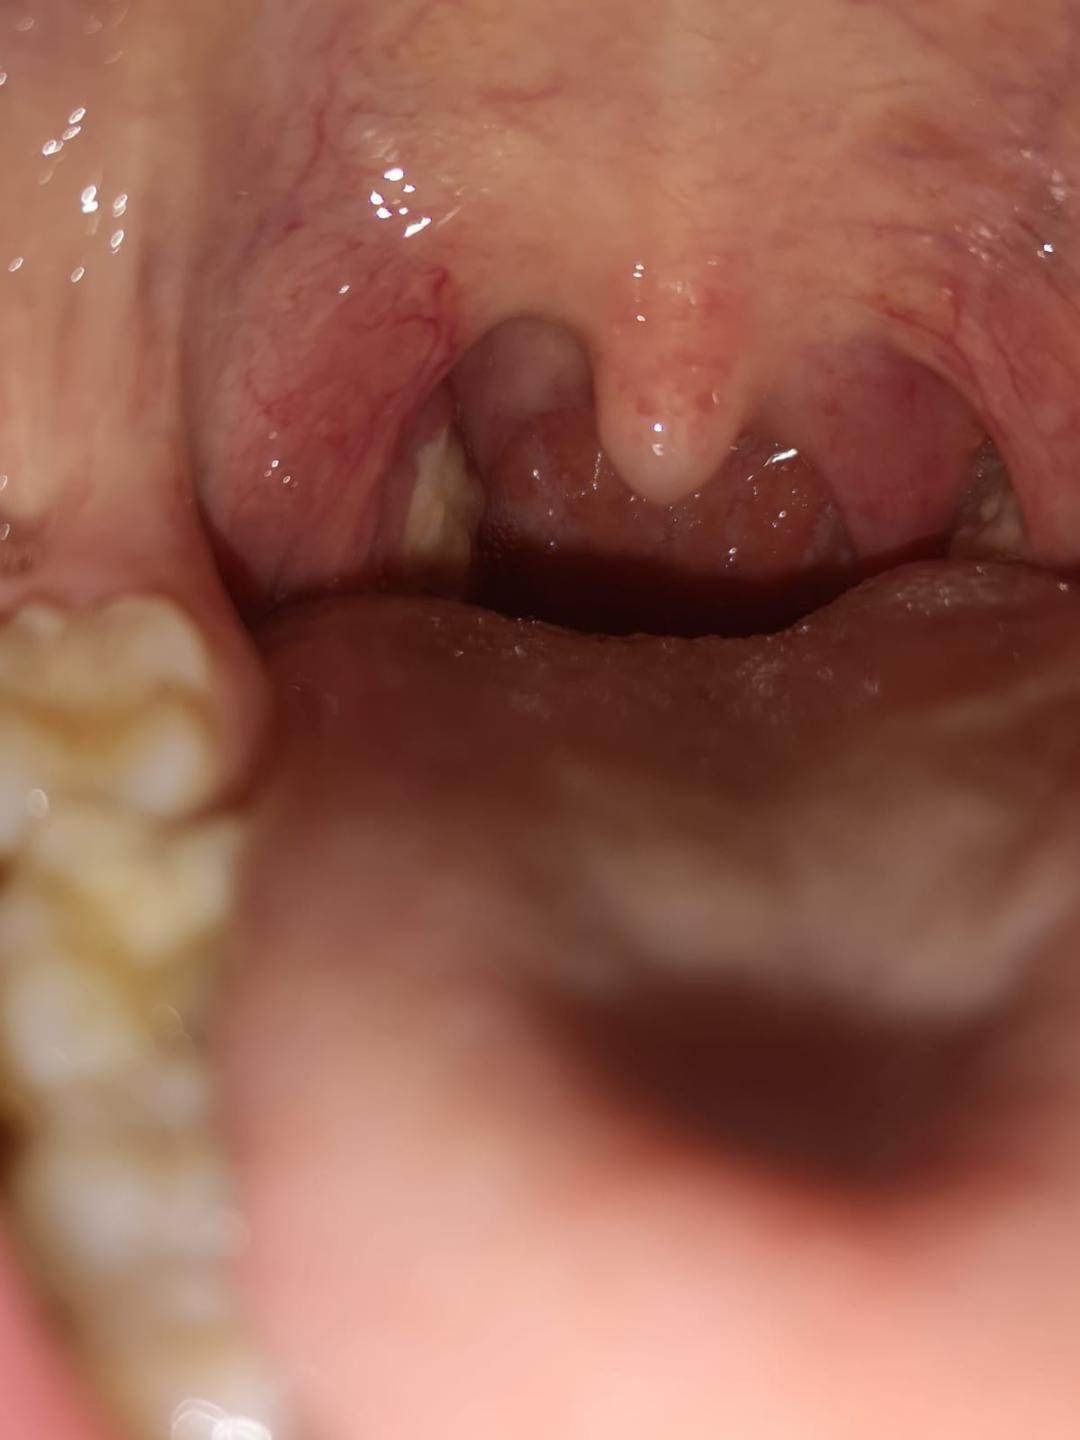

Poza 2- Status 10 zile postoperator (se remarca diminuarea semnificatica a volumului amigdalelor palatine precum si a criptelor amigdaliene)